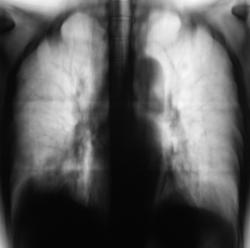

При расшифровке цифровых флюорограмм пациентка была "взята на контроль".

Произведено стандартное дообследование.

Жалоб пациент не предъявляет. Возникло сильное желание без промедлений направить пациентку на консультацию в ОКБ. Коллегиально решили провести противовоспалительную терапию, а затем "провести контроль".

После проведения противовоспалительной терапии проведен "контроль".

Ваше мнение уважаемые коллеги?

А млжет быть эти крупные очаги - метастазы?

По всей видимости, придется направить на консультацию к онкологам.